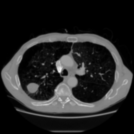

Aside from quantitative results, we provide a principal component analysis (PCA) visualisation of the 3D embeddings of Merlin, CT-FM, CT-CLIP, and our COLIPRI-CRM encoder, on a lung cancer case from the MSD Lung dataset (Fig. 1). The embedding resolution is very low for Merlin and CT-FM, providing hardly any semantic localisation. CT-CLIP yields embeddings of higher resolution, allowing features to be visually mapped from the input CT to the PCA map. However, the PCA map is inconsistent and noisy, and exhibits a strong bias towards absolute position within the scan, as visible through the anteroposterior green/red shift. On the other hand, our COLIPRI encoders yield higher-resolution embeddings, which are sharper and more consistent, allowing for clear recognition of the boundaries of the patient, lungs, and the abdominal organs, as well as the lung mass present in the right lung (on the left-hand side of the coronal and axial slice views).